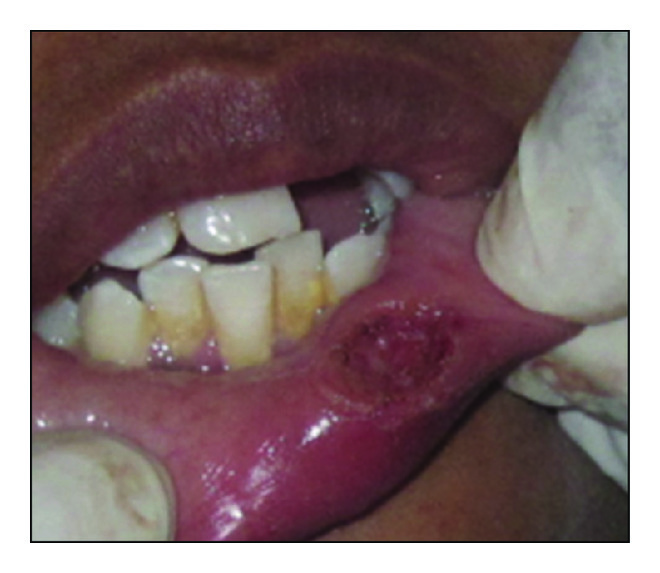

Following minimal infiltration of 1 : 2,00,000 Xylocaine, the lesion was excised using soft diode laser in wavelength of 940 nm, 400 μm diameter tip at 1.5 W in continuous mode. The incision was placed on the uppermost site of the lesion and complete excision was performed (Figures 2, 3(a), and 3(b)). The specimen (Figure 4) was subjected to histopathological examination and showed cystic cavity lined by thick fibrous capsule. Cystic lumen contains mucin, foamy macrophages, and chronic inflammatory cells. Areas of coagulation necrosis surrounding the intended biopsy material were also evident. Adjacent mucous salivary gland was also seen. With all these histopathological features, diagnosis of mucous extravasation cyst was given (Figures 5 and 6). Patient was prescribed analgesics. There was uneventful healing on 45 days of follow-up (Figures 7, 8, 9, 10, and 11).